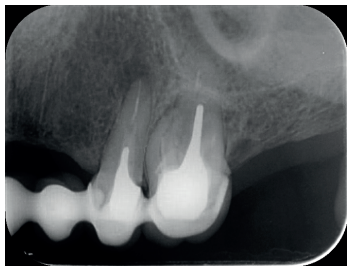

El paciente aporta como estudio radiológico una ortopantomografía (OPG), (Figura 1). Se realizaron radiografías periapicales (Figuras 2 y 3), así como exploración clínica incluyendo la valoración periodontal de los dientes afectados, sin observar profundidades de sondaje aumentadas que pudieran indicar la existencia de lesiones endoperiodontales.

Para el correcto diagnóstico de lesiones radiolúcidas a nivel periapical es importante disponer de imágenes radiológicas que muestren con precisión la situación y tamaño de dichas lesiones. En nuestro caso el paciente aportaba una ortopantomografía. Este tipo de radiografía no es adecuada para el diagnóstico en endodoncia. La radiografía periapical aporta mejor definición, especialmente a nivel anterior, ya que presenta una menor distorsión. Actualmente el CBCT es la prueba radiológica más fiable, ya que proporciona imágenes en las tres dimensiones del espacio, lo que permite diagnósticos más precisos1,2 .